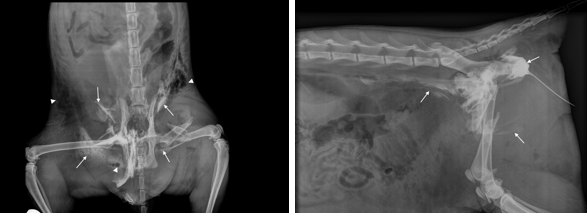

What is being shown here?

RTA —> femoral #

Bladder rupture —> leakage of urine into the peripheral tissues

cannot see clear bladder outline

gas obacity in abdomen, consistent with ruptured ureter